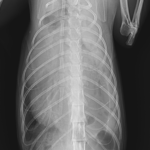

保護した猫さんの呼吸が早いかも??? かかりつけの先生に相談されたようです。エックス線検査で横隔膜ヘルニアが確定されました。外科的な対応を希望され来院されました。肝臓のほとんどが胸腔内にヘルニア(逸脱)しており、開腹アプローチで横隔膜を整復しました。正しい位置に臓器が戻ったので、これからは呼吸が楽になります。